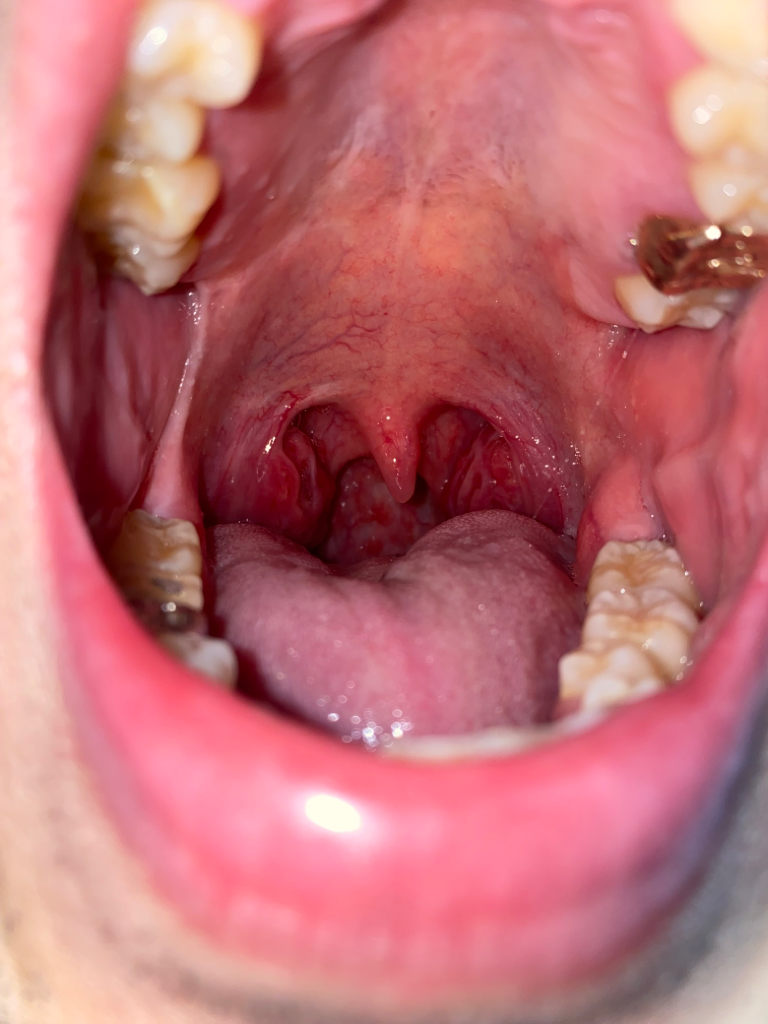

아침 양치할때와 식사후에 침에 피가 섞여 나온지 엄청 오래돼서 코, 목, 폐 등 다 검사를 받았는데 이상이 없다고 합니다. 그러다 거울을 보는데 편도쪽이 헐어서 피같은게 보이고 오른쪽(사진상에서는 왼쪽) 볼과 윗 어금니와 아래 어금니 연결된 부분(후구치 삼각 부분)이 하얗게 상처난듯이 모양과 색이 변해있었습니다. 이것도 꽤 오래 됐어요 한 1년? 평소에 볼을 자주 씹습니다 ㅠ 그리고 오른쪽 편도쪽으로 통증 있고 자극적인 음식 먹으면 작열감도 생깁니다 ㅜ

혹시 구강암일까요?? 어제 대학병원에서 코쪽 내시경과 머리ct 찍었는데 이상 없었습니다 ㅠ

귀하의 경우, 입 안 오른쪽 볼과 후구치 삼각 부분이 하얗게 변하고, 침에 피가 섞여 나오는 증상이 있으므로, 구강암의 가능성을 배제할 수 없습니다.

그러나, 귀하는 이미 코, 목, 폐 등 구강암이 발생할 수 있는 다른 부위에 대한 검사를 받았고, 이상이 없다고 하셨습니다. 또한, 대학병원에서 코쪽 내시경과 머리 CT를 찍었지만, 이상이 없었다고 하셨습니다.